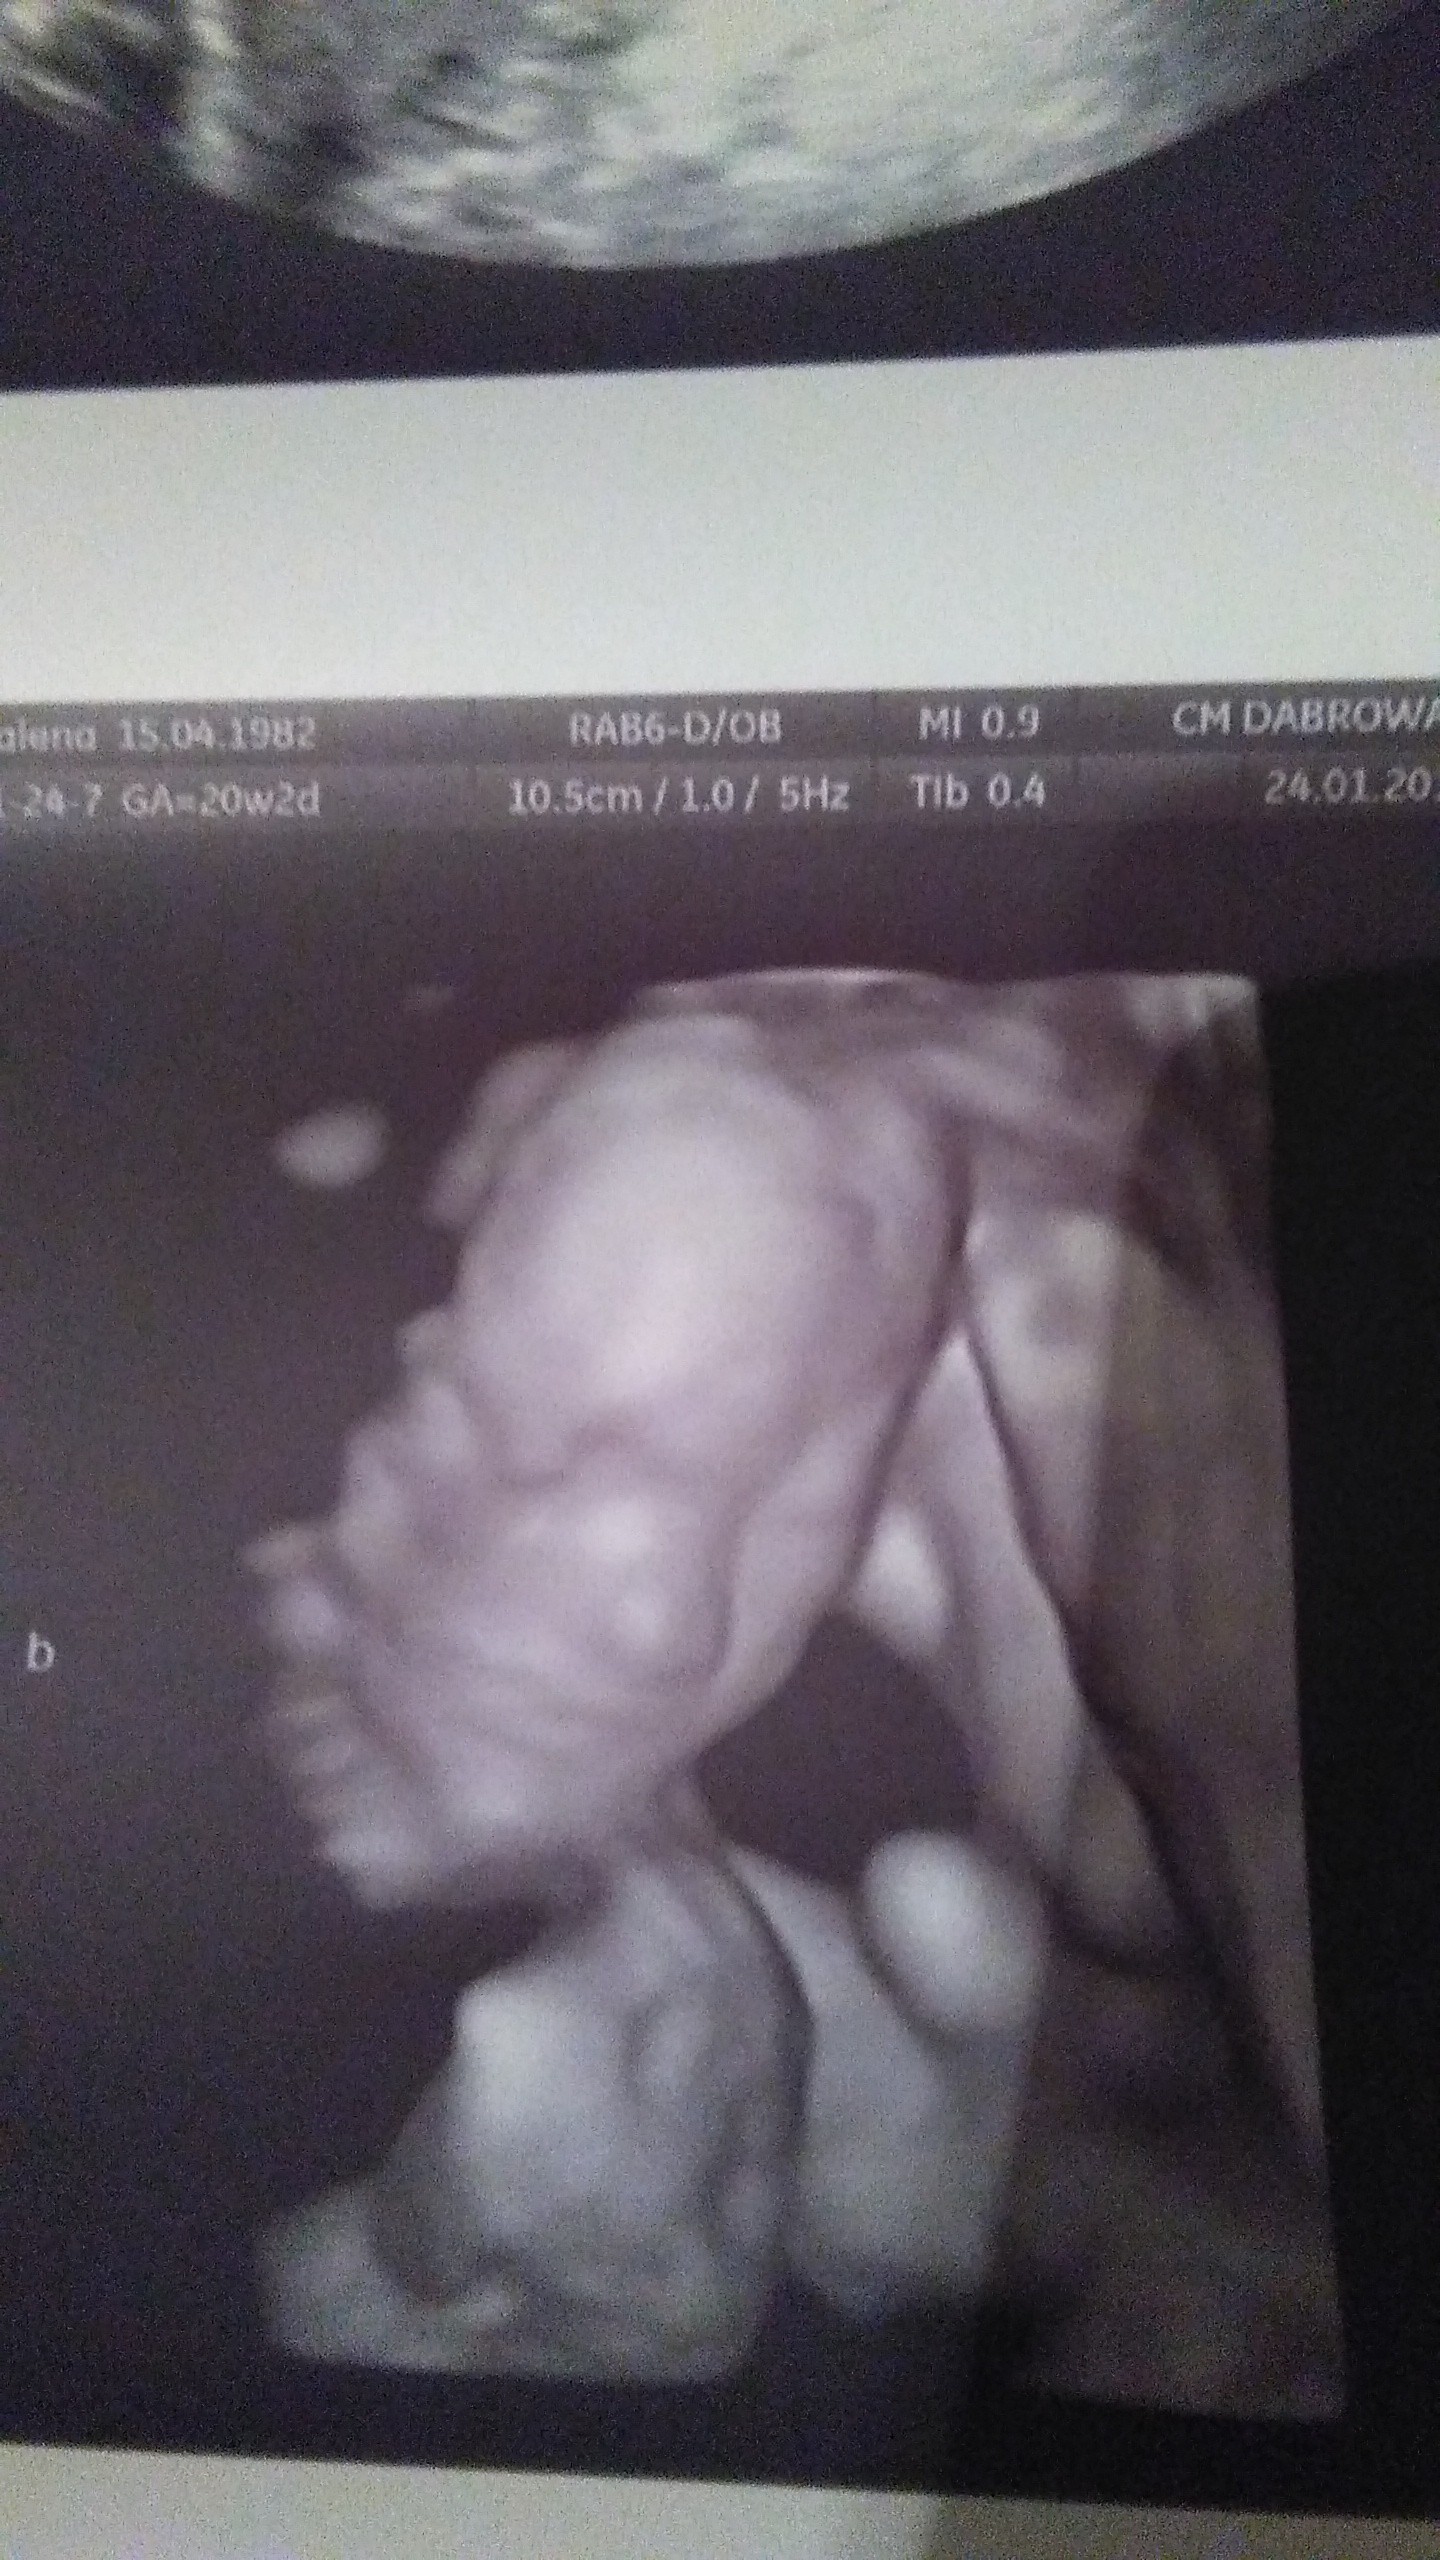

Dziewczyny walczcie dzielnie o swoje marzenia. Jako przykład przedstawiam wam mój mały wielki cud - bliźnięta jednojajowe. 20 tydzień. Trzeci transfer, podana najslabsza blastusia, która w dodatku podzieliła się i oto mamy - Olę i Izę

Zobacz załącznik 936699Zobacz załącznik 936700